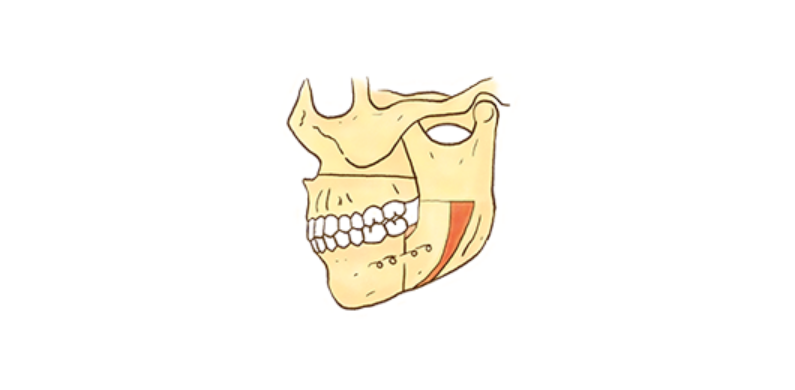

수술 교정

일반 교정 치료만으로는 개선이 어려운 골격을 변화시키는 심미성이 우수한 교정 프로그램입니다.

턱 수술과 교정 치료를 병행하여 치료하는 것으로 주걱턱, 안면 비대칭, 무턱, 돌출입 등과 같은 증례에서 주로 이루어지며,

하악 수술 또는 양악 수술이 시행됩니다.